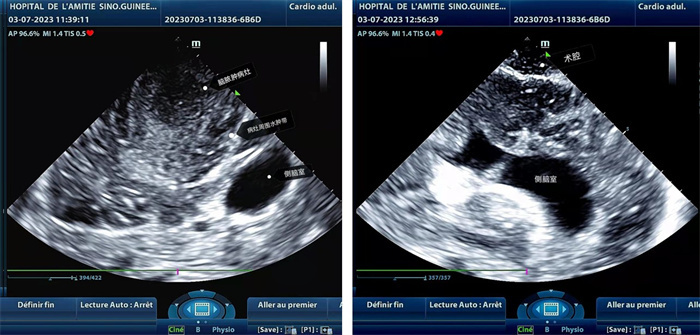

手術(shù)中,張國濱在超聲科顧秀娟的幫助下,運用顱腦術(shù)中超聲技術(shù),通過將一次性保護(hù)套的超聲探頭置于腦組織表面,實時觀察病變的位置和形態(tài),進(jìn)一步確認(rèn)最佳手術(shù)路徑。術(shù)中超聲顯示,病變位于左額頂葉,大小約為4x4x3cm,邊界清晰,呈囊實性,周邊腦組織水腫明顯。最終,病灶順利切除,診斷為腦膿腫,并通過超聲檢測確認(rèn)術(shù)腔無病變殘留、無出血,為患者術(shù)后恢復(fù)提供了良好的保障。

左圖顯示術(shù)中超聲見囊實性病變,大小約為4x4x3cm,病灶周圍腦組織水腫明顯;右圖為病灶切除后,術(shù)中超聲示術(shù)腔無病變殘留。中國第二十九批援幾內(nèi)亞醫(yī)療隊供圖